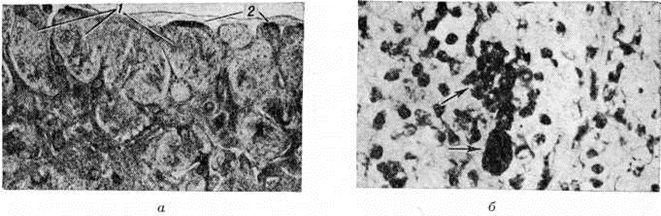

Патогистология. Капсула лимфатических, узла сохранена, периаденит отсутствует. Структура узла, как правило, не нарушена. Иногда она может быть стёртой. В корковом веществе — скопление ретикулярных клеток с веерообразно расположенными новообразованными капиллярами. Синусы сохранены, хотя нередко бывают замаскированы воспалительным инфильтратом, состоящим из лимфоцитов и в меньшей степени эозинофилов, нейтрофилов и плазматических клеток. Лимф, фолликулы могут быть гиперплазированы (рисунок, а), однако в периферических зонах лимфатических, узла они чаще кажутся атрофичными в результате их сдавливания ретикулярными клетками. В большинстве случаев часть ретикулярных клеток содержит фагоцитированные меланин, липиды, иногда гемосидерин. Меланин обнаруживается и внеклеточно (рисунок, б).